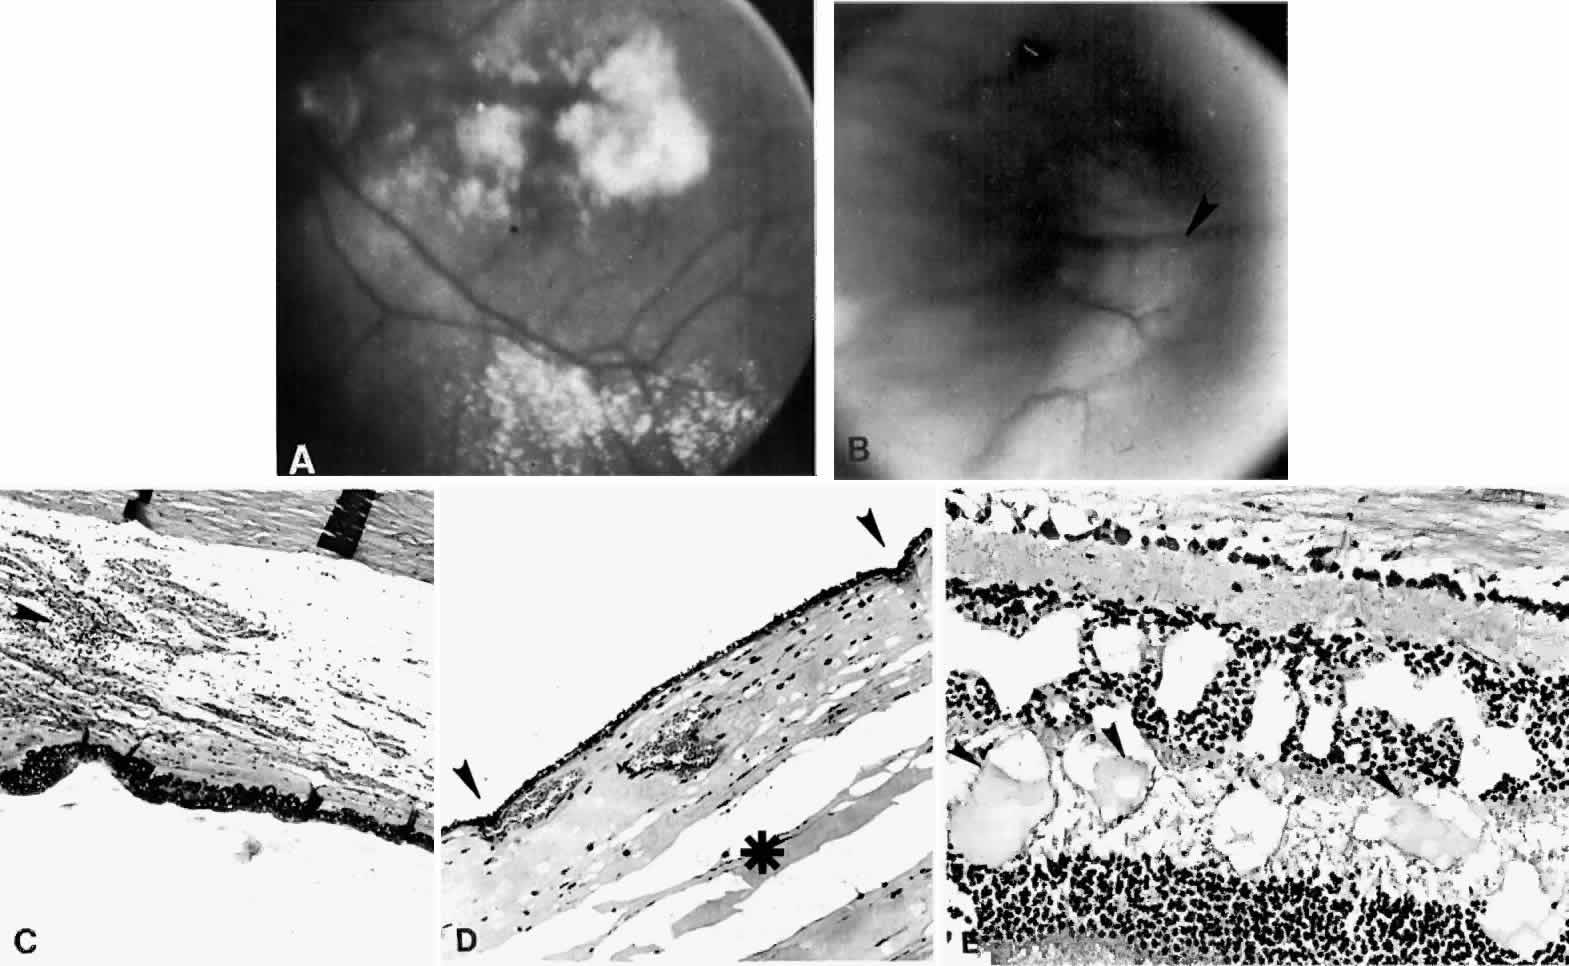

Fig. 15. A spontaneous ciliochoroidal effusion was mistaken for a malignant melanoma in a 61-year-old woman who presented with pain, blurred vision, keratitic precipitates, and aqueous cells and flare. A. Gross appearance of the ciliochoroidal effusion (large arrowheads). Small whitish inflammatory nodules are present in the choroid (small arrowheads). The apparent retinal detachment is artifact. B. An extensive ciliochoroidal effusion (asterisk) with a moderately intense chronic inflammatory cellular infiltration. (H & E, × 20). C. The choroid viewed posteriorly, showing occlusive granulomatous vasculitis (arrow) and an intense lymphocytic infiltration crowding the choriocapillaris. The retinal pigment epithelium is intact (H & E, × 290). D. Intense lymphocytic infiltration of choroid, inner scleral lamellae, and episclera (H & E, × 55). E. Diffuse scleritis viewed posteriorly, showing perineural lymphocytic infiltration in the episclera and within a scleral canal (arrowheads) (H & E, × 55).

Histopathologically, there is a variable lymphocytic infiltrate in the ciliary body and choroid (see Figs. 19 and 20; Fig. 21).96